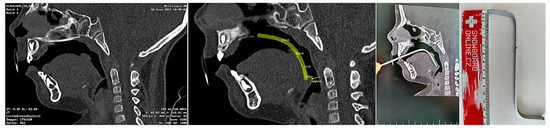

The invasiveness of the presented concept lies in the necessity of the initial CT scan, albeit some experts do not consider x-ray examination as an invasive examination method. CT uses ionizing radiation that may cause damage to DNA, and children are at greater risk of carcinogenesis due to their higher tissue radiosensitivity and their longer life expectancy compared to adults. The costs and benefits of the examination for the patient must be clear. In life-threatening situations involving severe craniofacial syndromes, a CBCT or CT scan is performed working from other indications. Figure 7. shows the intention of pediatric otorhinolaryngology department to provide orthodontists with a guide for the approximate ideal length of the spur, visualized on the sagittal slice of the CT scan (Figure 7). The method presented in this paper provides information about 3D patient virtualization. The airway entry with the spur must recognize not only a potential maxillary cant, but also any asymmetries or lateral excursions of the airway where the spur will be oriented. A majority of these can be evaluated without the necessity of CBCT/CT diagnostics. This paper does not define 3D x-ray examination as a necessity. The described method enables 3D design based on segmented CT or CBCT scan.

Segmentation of the airway in the area between the nasopharynx and oropharynx is important to plan the spur’s position, especially in craniofacial syndromes with palatal cleft. Figure 8 shows a CT image of the segmented airway showing the complete morphology from the epiglottis up to the nasopharynx.